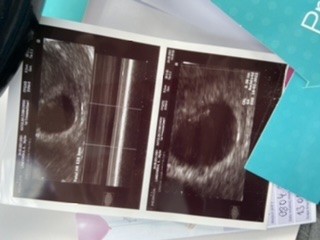

A to jest druga ciąża , obecnie 16t1d od początku do 15tc na duphastonie Zobacz załącznik 1300059

Pięknie, ni tu widać naprawdę spore ładne okrągłe jajeczko. Odpoczywaj duzoTaj pierwsza ciąża , może nie łezka ale taka jakby fasolkaciąża od poczatku bezproblemowa

I ta ze sporym okrągłym jajeczkiem jest bardziej „ problemowa „ bardziej mi daje w kośćPięknie, ni tu widać naprawdę spore ładne okrągłe jajeczko. Odpoczywaj duzo![]()